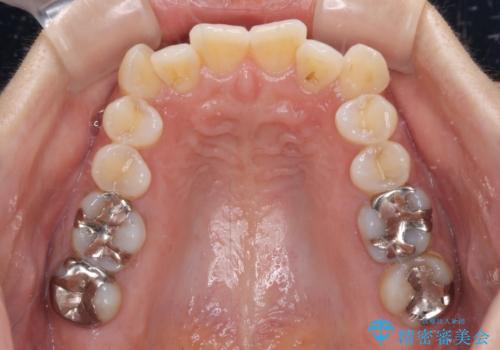

- 上顎の八重歯と全体的なデコボコを気にして来院された患者様です。

口元の突出感はなかったため非抜歯矯正での対応となりますが、八重歯を改善する際に上顎前歯が前突する可能性があったため、上顎臼歯部にアンカースクリューを使用して、歯列が前方に転位しないようにすることとしました。